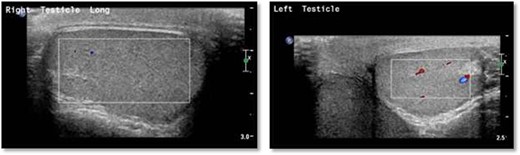

Scrotal Doppler ultrasound shows the size, echogenicity and vascularity is maintained for both testicle with slightly reduced in the right testicle that could be suggestive of right torsion/detorsion.

An 18-year-old healthy man presented to the emergency department (ED) with 1-day history of right testicular pain and vomiting with no fever nor abdominal pain. Physical examination showed mild tenderness in the right testis, no swelling, normal longitudinal position and cremasteric reflex. Scrotal Doppler ultrasound was performed and showed reduced vascularity in the right testis and the left testis was normal. Moreover, the size and echogenicity were maintained for both testes (Fig. 1). Two months prior to this presentation, the patient presented with the same attack with only mild tenderness in the right testis, and all investigations were within normal limits and he was discharged with oral analgesic drugs. The decision was made to undergo surgical exploration for possible torsion/detorsion of the right testis. The patient was transferred immediately to the operating room for bilateral orchiopexy. The right spermatic cord was engorged with no evidence of ischemia identified and bilateral orchiopexy was done successfully. After the surgery, the patient was kept for observation for 24 h and then discharged. After 2 days from the surgery, the patient came back to ED with testicular pain and post-surgical swelling. We decided to do computerized tomography (CT) scan of the abdominal and pelvis to rule out retroperitoneal pathologies or referred pain. The CT showed 4 × 3 cm lobulated mass noted at right paravertebral space invading the right psoas muscle at the level of L3 and L4 (Fig. 2). The CT scan also showed there is an associated fistula tract between the mass and infrarenal inferior vena cava with thrombosis associated with epidural component extending through the neural foramina compressing the spinal cord from the level of the L2–L4 (Fig. 3). The patient was referred to spinal surgery and CT-guided paraspinal lumbar biopsy was taken. The histopathology came with the diagnosis of Ewing sarcoma. The decision was made by the medical oncology to start on a systemic chemotherapy (vincristine + Adriamycin + cyclophosphamide alternating with ifosfamide + etoposide (VAC/IE)) regimen. After six cycles, the follow-up magnetic resonance imaging demonstrated significant resolution of the right psoas and posterior paraspinal metastatic disease. In addition, further resolution with residual intraspinal extradural metastatic disease noted at right L2–3 and L3–4 levels. The patient is still followed up as an outpatient clinic with medical oncology.